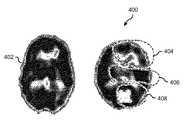

図5は、実施形態に従った、関心領域を有する磁気共鳴画像法の脳スキャン画像を示す。スキャン画像400は、磁気共鳴画像法による患者の脳のスキャン画像である。これに対し、スキャン画像402は、磁気共鳴画像法による健常者のスキャン画像である。スキャン画像400は、関心領域404〜408を有する。関心領域404〜408は、スキャン画像400内の領域であって、潜在的な状態、異常、化学的不均衡、疾病、又は当該スキャン画像の期待される外観からの他の偏差の兆候を示す。この例では、関心領域404〜408は、脳活動の崩壊を示す。領域406は、脳室のサイズの異常な変化を示す。領域408は、前額断の減少した機能を示す。  FIG. 5 shows a magnetic resonance imaging brain scan image with a region of interest, according to an embodiment. The